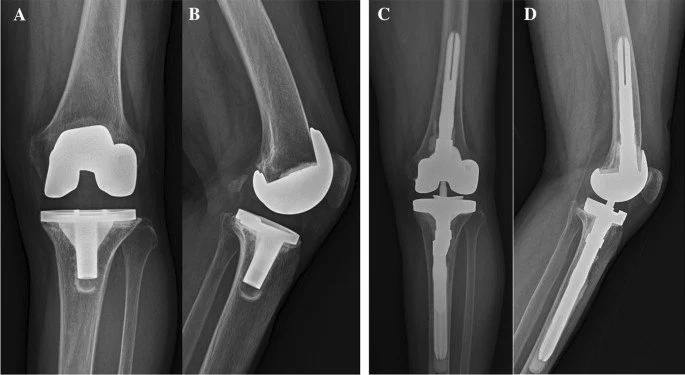

Implant Choice in Revision TKR

Revision TKR typically requires specialized implants designed to manage issues like bone loss, instability, and complex anatomy. Options include:

- Modular Implants: Modular designs allow for a tailored fit to accommodate individual bone deficiencies and ligament imbalances.

- Constrained Implants: These implants provide enhanced stability in cases of ligament deficiency or instability.

- Augments and Stems: Augments are used to fill bone defects, while extended stems offer additional support within the bone. Both components provide stability in areas affected by bone loss or implant loosening.